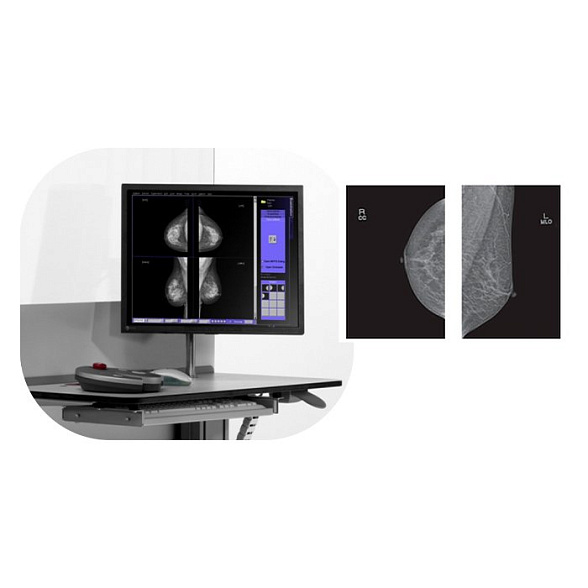

Bemems Pinkview АT Маммограф с комплексом компьютерной радиографии

Bemems Pinkview AT: Цифровой маммограф с комплексом компьютерной радиографии

Маммограф Bemems Pinkview AT представляет собой современную цифровую систему для ранней диагностики заболеваний молочной железы. Это комплексное решение, объединяющее в себе высокотехнологичный маммографический аппарат и рабочую станцию компьютерной радиографии (КР), что обеспечивает полный цикл получения и обработки диагностических изображений.

- Повышение производительности: Мгновенное получение изображения на монитор врача исключает время на проявку пленки, ускоряя процесс обследования и снижая вероятность технического брака.

Встроенная система компьютерной радиографии — это не просто сканер, а интеллектуальное звено, преобразующее информацию с imaging plate (CR-кассеты) в цифровой DICOM-файл. Комплекс включает в себя считывающее устройство, рабочую станцию со специализированным программным обеспечением для обработки и просмотра изображений, а также набор многоразовых CR-кассет. Это решение идеально подходит для модернизации существующих пленочных маммографов до цифрового уровня или для создания гибкой диагностической сети.

| Режимы съемки | Стандартные проекции: краниокаудальная (CC) и медиолатеральная косая (MLO). Возможность прицельной и увеличенной маммографии. |

| Программное обеспечение | Включает ПО для управления аппаратом, считывания CR-кассет, обработки, просмотра, архивации и передачи DICOM-изображений. |

Входит ли в комплект рабочая станция врача?

Да, комплекс компьютерной радиографии включает в себя рабочую станцию (компьютер, монитор медицинского класса, считывающее устройство и ПО), необходимую для обработки и анализа полученных изображений.